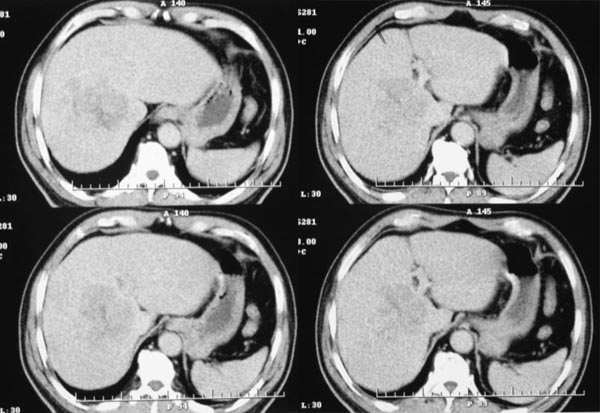

患者,m,71y,乏力、纳差、巩膜黄染两月余,b超示肝内占位性病变。

平扫

1.临床资料:71y,乏力、纳差、巩膜黄染两月余。

2.病灶特点:平扫呈低密度,密度不均,中央呈更低密度;动脉期病灶周围强化较明显,高于正常肝组织,低于同层主动脉密度,中央坏死区未见明显强化;门静脉期,病灶呈低密度,低于正常肝组织密度。

3.诊断:符合肝细胞癌。

临床:患者,m,71y,乏力、纳差、巩膜黄染两月余,b超示肝内占位性病变。

病灶特点:1、平扫:肝右叶大片状低密度影,内见更低密度影,边界不清

早期强化不是很明显,血供不是很丰富,与肝实质相比还是呈快进快出的特点,中心裂隙样坏死,支持原发性肝癌。